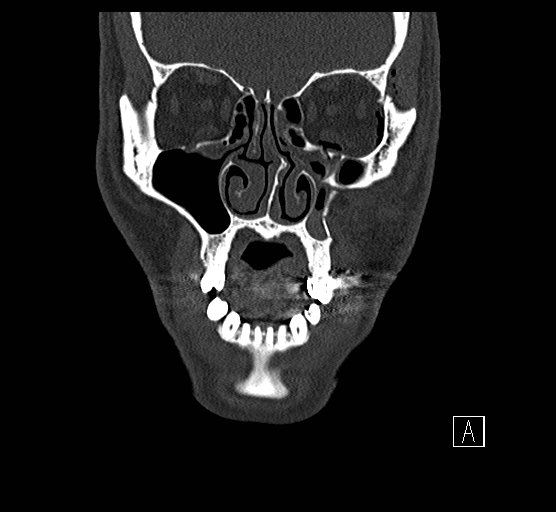

Physical exam showed marked left palpebral subcutaneous crepitus, as well as bulbar and palpebral conjunctival bulging. Visual acuity was normal with intact extraocular movements, and normal pupillary exam. Computed tomography (CT) imaging of the face was obtained and revealed multiple displaced fractures involving the left orbital floor and zygomatic arch associated with moderate periorbital and postseptal extraconal gas, resulting in orbital proptosis.